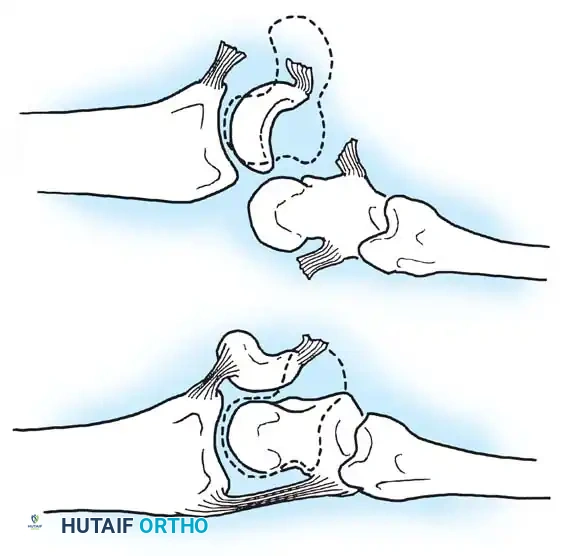

Fig. 66-77 A, Normal scapholunate and capitolunate angles. B, DISI deformity. C, VISI deformity.

1. Dorsal Intercalated Segment Instability (DISI): The distal articular surface of the lunate tilts to face dorsally. This is the hallmark of scapholunate dissociation.

2. Volar Intercalated Segment Instability (VISI): The distal articular surface of the lunate tilts toward the palm. This is typically associated with lunotriquetral dissociation.

Linscheid et al. emphasized the critical importance of the true lateral radiograph. In a normal wrist, the longitudinal axes of the radius, lunate, capitate, and third metacarpal should be collinear within an approximately 15-degree tolerance.

When ligamentous disruption occurs, predictable collapse patterns emerge: